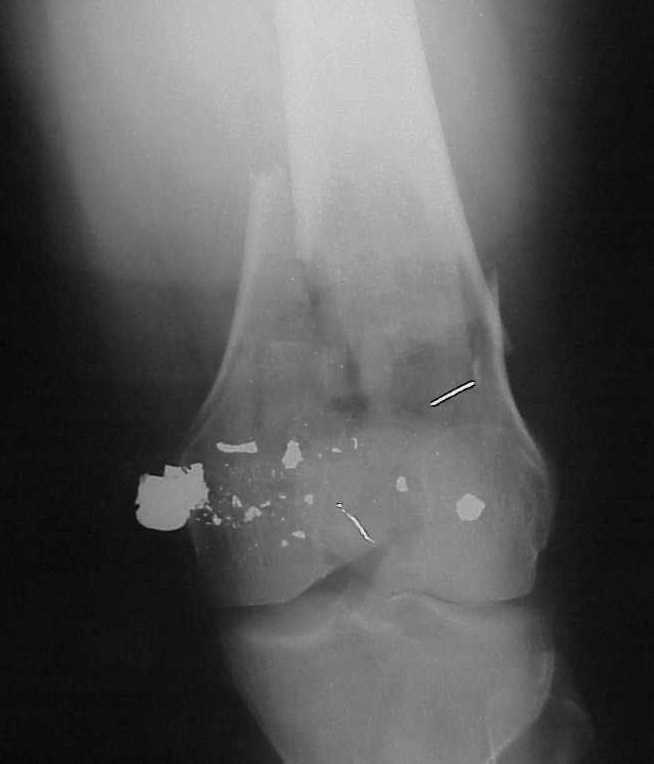

A CT and knee xrays would help identify lateral condyle comminution and/or a "hoffa fragment" of the posterior condyle. I am concerned that the lateral cortex is not sufficient to give purchase for a retrograde IMN. blocking screws could improve this as a possibility. A long blade or LISS if avaible would be my secondary choices. Good luck. Any chance you can get these cases transferred earlier when it

Насчет стабильности для ранней нагрузки, конечно, сомнительно, но при таком повреждении ранняя нагрузка противопоказана в любом случае. Для ранних движений Должно хватить. Снимки в следующем сообщении.

воспользовались для репозиции, см. приложение.